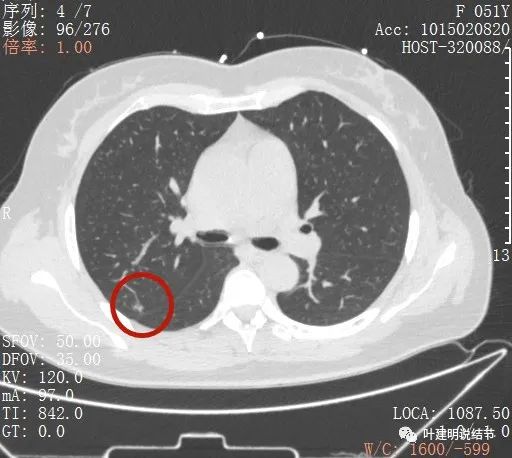

從平掃看,病灶雖然小,但就不舒服,極可能是惡性的。我們再來看她其餘部位還有小結節:

上葉後段另有一磨玻璃結節,約5-6毫米許,密度低,瘤肺邊界清,考慮不典型增生或原位腺癌可能性大,但目前風險程度低

右上葉後段還有一微小結節,約1-2毫米,密度不高,瘤肺邊界清,考慮也是原位腺癌可能性大,目前風險程度低